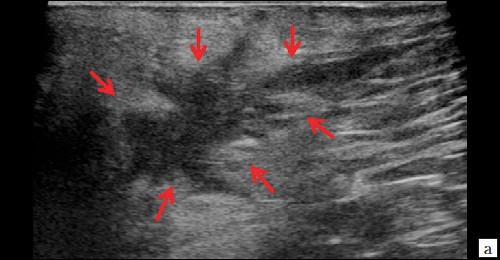

Описываемое образование прилежит к передне-боковой утолщенной стенке анального канала, нечетко от нее дифференцируется (см. рис. 1, а, б). По периферии образования – выраженная сосудистая реакция (см. рис. 1, в). По периферии образования ближе к ягодичной области – формирующийся свищевой ход размером 1,3×0,6×0,6 см (см. рис. 1, г).

Рис. 1. а, б – В-режим. В перианальной области слева на глубине 0,6 см от поверхности кожи определяется гипоэхогенное жидкостное образование с четкими неровными контурами с наличием неоднородного гиперэхогенного подвижного содержимого размером 3,9×2,1×1,9 см, объемом 8,24 мл с утолщенными до 0,3 см стенками. Описываемое образование прилежит к передне-боковой утолщенной до 1,0 см стенке анального канала, нечетко от нее дифференцируется (стрелки);

г – В-режим. По периферии образования ближе к ягодичной области – формирующийся свищевой ход размером 1,3×0,6×0,6 см (стрелки).